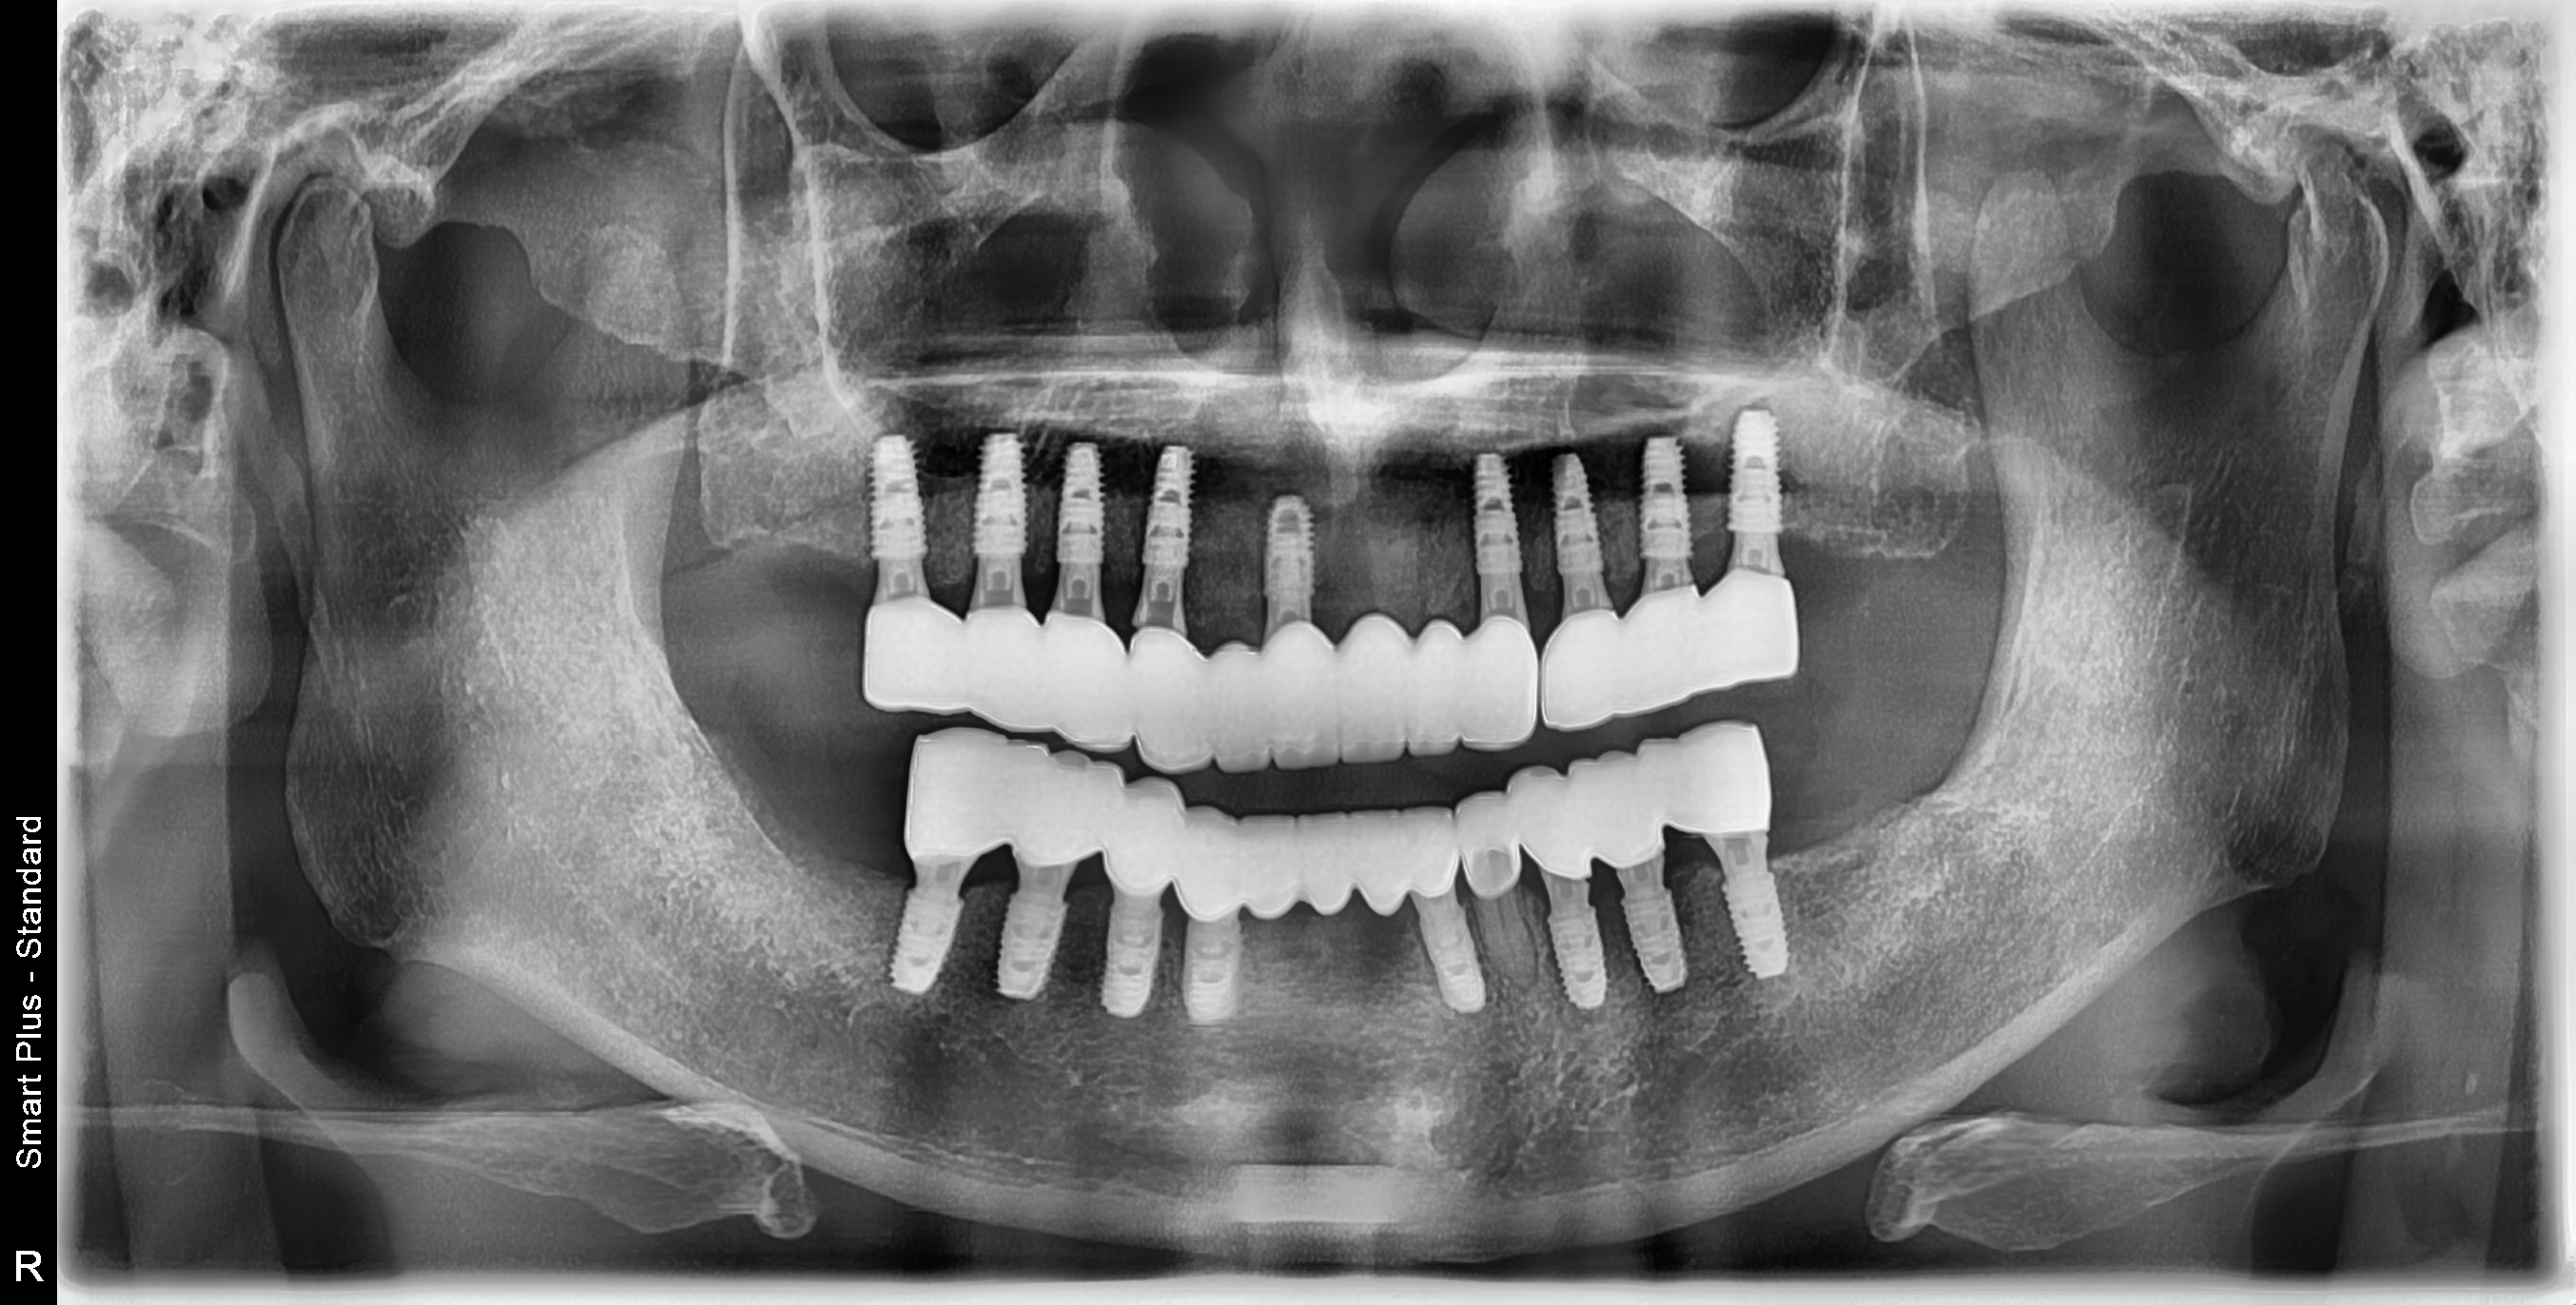

After